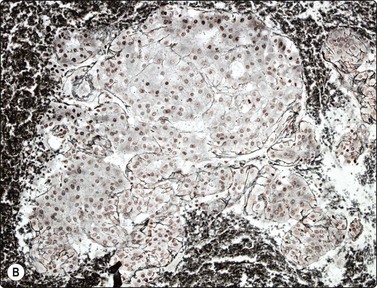

image

Fig. 10.25 Hepatocellular carcinoma

CD34 immunostaining demonstrates the classic endothelial staining pattern which is absent in reactive liver cell block (CD34, HP).

CD34 and factor VIII immunostaining have been used in demonstrating the classic endothelial staining pattern of HCC (Fig. 10.25), absent in reactive liver and metastatic carcinoma,139 but are limited by partial staining of adenoma and focal nodular hyperplasia. Indeed, they provide little more information than the less expensive reticulin.131,139-141 Over-expression of Glypican-3, a heparan sulphate proteoglycan that plays an important role in cell growth and differentiation, has been observed in malignant hepatocytes. In several studies on cytological smears, positive staining for Glypican-3 showed a high sensitivity (80–90%) and specificity (> 95%) in HCC versus metastatic tumors and benign liver lesions.142-144